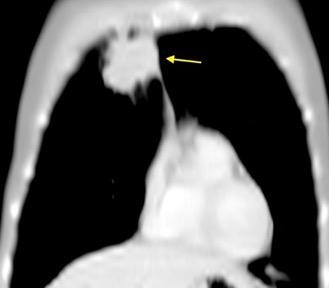

De los pacientes con Tumor de Pancoast

1,7% tienen una radiografía de tórax normal

Fletcher F et al. The normal chest radiograph in bronchial carcinoma. Br Med J. 1976